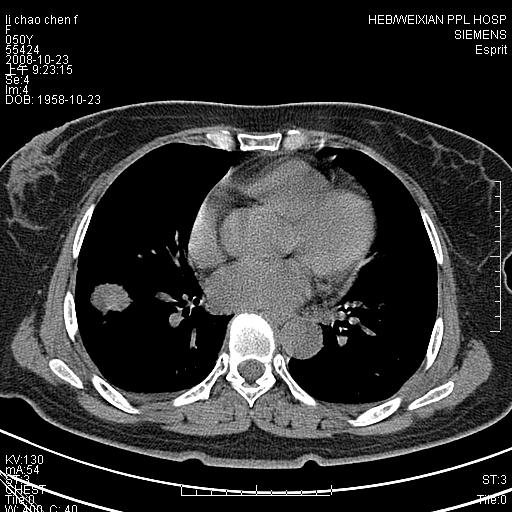

体检发现肺部肿块,现无不适。五年前曾有过哮喘病史。

先对现有的图象资料谈几点看法:病变位于右肺下叶前基底段,上部呈类圆形改变,分叶及毛刺征象不明显,下部呈不规则气腔改变,近肺门侧可见与一粗大血管相连,考虑为引流静脉影.其他肺叶相对正常所见.分析:该病灶良恶性均有可能.(现有资料来说).强化及穿刺活检有助鉴别.

考虑右肺下叶前基底段周围型肺癌可能性大。

右肺下叶前基底段占位性病变,不排除周围型肺癌可能,尽快手术为妙。

右肺下叶前基底段周围型肺癌可能性大。